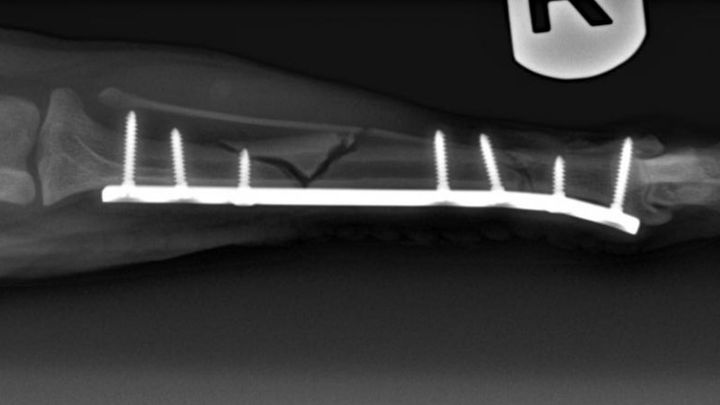

During our holiday trip up to NorCal to visit family, our beloved little chihuahua, Chiqui, that many of you know and love, was involved in an accident which resulted in her right, back leg being broken fairly severely. The break and additional fracture occured in both her tibia and fibula bones and were extensive enough to require an expensive surgery and recovery process: about $1,500 for the initial emergency care and hospitalization and $5,500 for the surgery and medication.